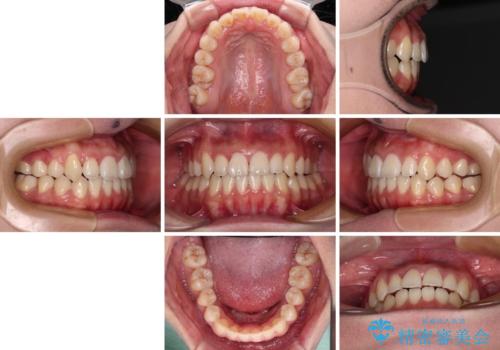

上顎骨を拡大することで、八重歯やデコボコを歯列に収めることができ、下顎の歯が外に位置していた奥歯の咬み合わせも改善することができました。

スペースも短期間に獲得できるため、1年程度で治療を終えることができました。